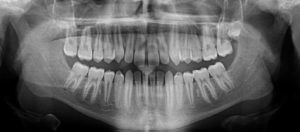

A 12 year old Caucasian male presents with a chief concern that “I don’t like my overbite”